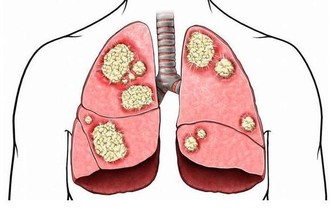

長久以往身體的狀態就有可能會受到或多或少的影響,雖然維生素是一種非常好的營養補充劑,但若是補充過量不僅不會給身體帶來益處,

但是維生素C服用過量仍可產生一些不良反應,